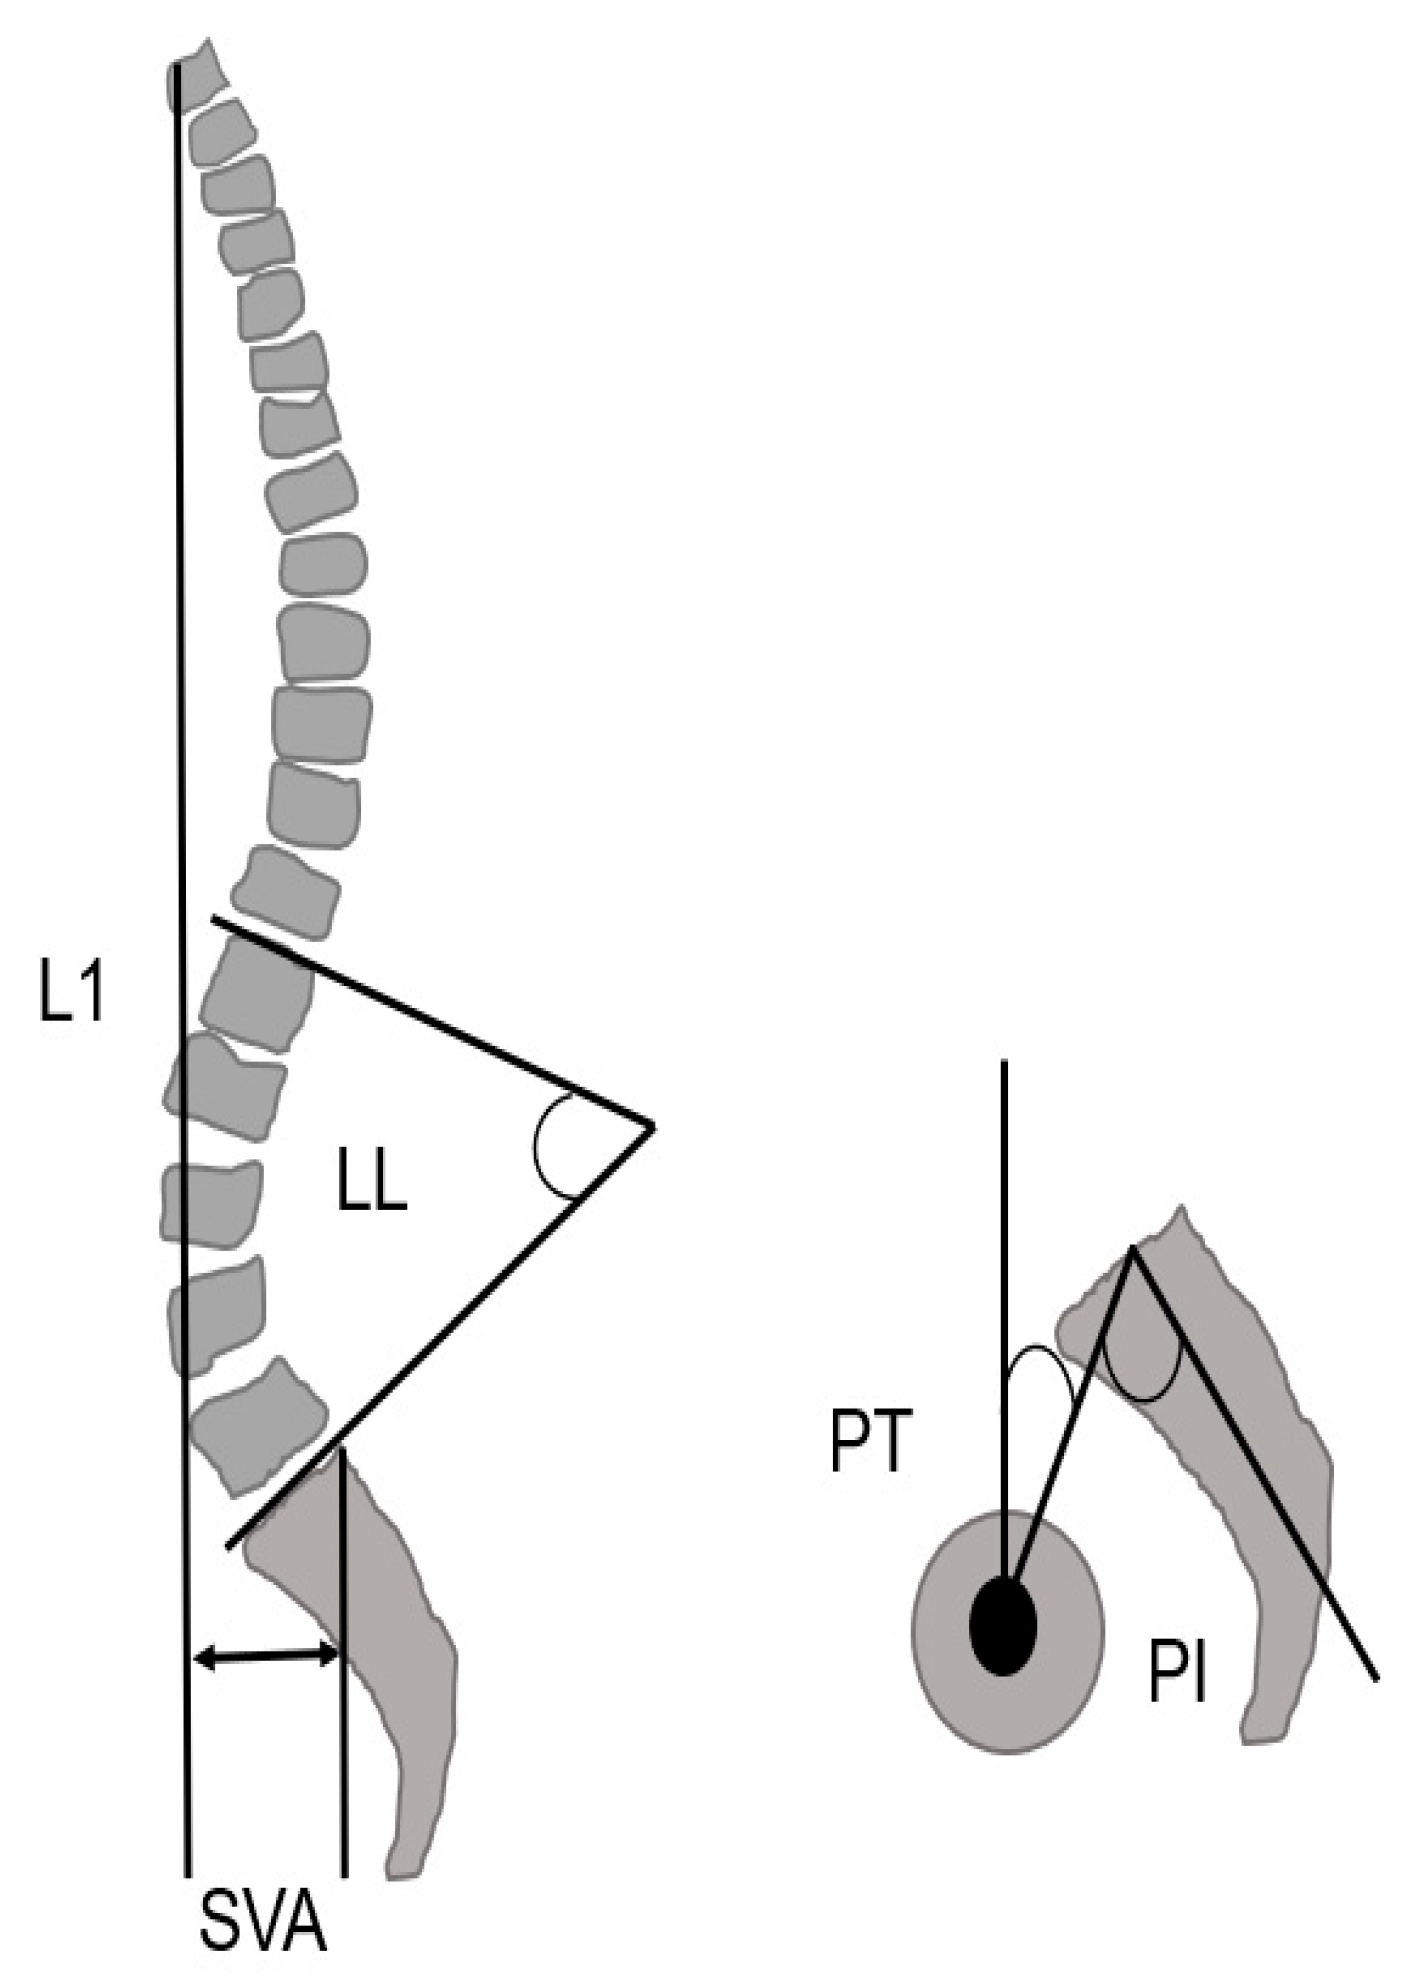

2.3. Radiographic Measurements

3.3.3. Spinopelvic Parameter